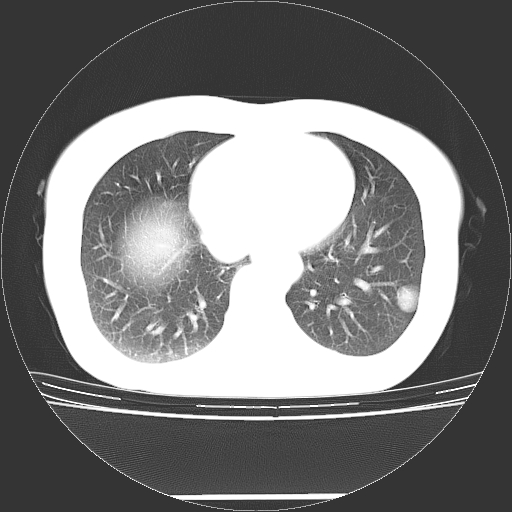

标题: CT27224:女,43岁,体检发现左肺下叶结节影。 [打印本页]

女,43岁,体检发现左肺下叶结节影。

左下肺外带胸膜下见孤立实性均匀密度结节影,边缘光整,增强呈渐进性强化,病灶吴分叶征及毛刺征象;支持硬化性血管瘤。

良性结节,有钙化,强化不明显,考虑软骨性错构瘤。

左肺下叶外基底段良性结节(错构瘤?)。